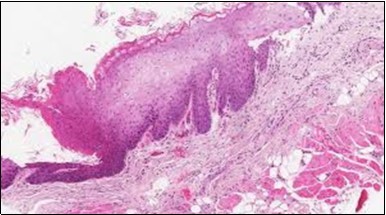

Figure 11.HCL Oral mucosa with soft tissue infiltration of hairy cells(27).

The classic hairy cell is medium sized with a magnitude of 10-14µm. The moderately abundant or variable cytoplasm may be transparent or mildly basophilic. The cellular surface with the characteristic serrated perimeter depicts innumerable fragile or stout extensions of cytoplasm ,particularly discernible on the phase contrast and electron microscopy. The cytoplasm may exhibit vacuoles with occasional azurophilic granules4. The nucleus may be elliptical or reniform, folded or indented with a coarse, reticulated or a finely dispersed chromatin and inconspicuous nucleoli along with infrequent mitosis. Bone marrow aspiration or bone marrow trephine biopsy may be inadequate for diagnosis in 30%-50% individuals4. The trephine sections of the bone marrow may depict a characteristic interstitial pattern of leukaemic infiltration. Generally the bone marrow is hyper-cellular, though it may be hypo-cellular in 10-15% individuals4. The leukaemia cell ingress may be diffuse or partial, although diffuse infiltration is frequent. The partial variety of leukaemic dissemination may be ineptly categorized with an indeterminate differentiation from the uninvolved marrow. The malignant insertions may initially emerge as miniature, undefined, cellular loci. The formalin fixed, paraffin embedded sections may elucidate a crystalline zone or a “halo” appearance of the cells with a circumscribed nucleus on account of the plentiful cytoplasm4. The cellular margins may be intertwined. Fixation of bone marrow smears with Zenker’s fixative may demonstrate a retracted cytoplasm of the hairy cells with a consequent disconnected structure. The bone marrow in the absence of a malignant process may be hypo-cellular or hyper-cellular. Reticulin stains may delineate an enhanced accrual of broad, dense reticulum fibres surrounding the aggregates of leukaemia cells with the fibrous circumlocution of individual malignant cell and fibrotic extensions into the abutting, uninvolved bone marrow4.

The leukaemia cells may enunciate a characteristic immune phenotype, crucial for a confirmatory diagnosis. The peripheral blood mononuclear B cell population may display a kappa or lambda light chain restriction. The phenotype of classic hairy cell leukaemia may be delineated by concurrent, immune reactive CD19+ CD20+,CD 11c+, CD25+, CD103+ and CD123+. An intensely immune reactive CD200+ and a non reactive CD27- antigen may be present2, 4. Evaluation of a trephine bone marrow biopsy and bone marrow aspirate may define the degree of tumour infiltration. A dry tap on account of prominent bone marrow fibrosis may be elucidated at preliminary diagnosis. A decline in the normal haematopoiesis may account for a hypo-cellular marrow in 10% instances. Gradation of cellular infiltrating of the leukaemia within the bone marrow may be appropriately investigated with immune –histochemical stains2, 4. Immune staining for CD20+, annexin 1 and VE1 (a BRAF V600E stain] may validate the diagnosis and precisely analyse the extent of malignant bone marrow infiltration[8]. Determination of BRAF V600E mutation may be critical in therapeutically non responsive individuals with applicable standard therapy or in instances of multitudinous reoccurrences[9]. Deploying inhibitors of BRAF V600E gene may be efficacious in patients impervious to approved therapy. The mutation necessitates a comprehensive scrutiny of the implicated individuals with a sensitive molecular assay which may discern up to < 10% of the hairy leukaemia cells appearing in the peripheral blood smears or bone marrow aspirates diluted with peripheral blood or aspirates elucidating a dry tap[2,4]. Allele specific polymerase chain reaction (PCR) or a next generation sequencing may be optimally employed to circumvent false negative outcomes. If the leukaemia cells are sparse or if particularly sensitive & efficacious molecular techniques are not accessible, the application of appropriate immune histochemical stains to the bone marrow biopsy such as a BRAF V600E mutation stain (VE1) may detect the hairy cells and conclusively diagnose the condition[2,4,10]. Figure 1, Figure 2, Figure 3, Figure 4, Figure 5, Figure 6, Figure 7, Figure 8, Figure 9, Figure 10, Figure 11, Figure 12, Figure 13, Figure 14.